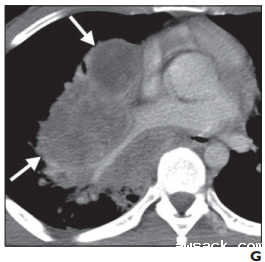

F-G图:

增强CT软组织窗下可见肿块明显增强及肿块内部中心坏死(实性箭头,F图)。肺动脉、静脉和右下叶支气管受肿块压迫,显示出严重狭窄(实性箭头,G)。所有这些特征均表明这是一种非常具有侵袭性的肿瘤,具有较高的增殖速率。经肺活检确认为NUT癌后,患者接受了两次卡铂和紫杉醇的化疗。但患者后期失去联系。

病例来源:

Bair RJ, Chick JF, Chauhan NR, French C, Madan R. Demystifying NUT midline carcinoma: radiologic and pathologic correlations of an aggressive malignancy. AJR Am J Roentgenol. 2014 Oct;203(4):W391-9. doi: 10.2214/AJR.13.12401. PMID: 25247968.(内容主要来源于原文献内容)